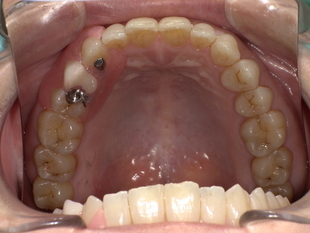

■ 【治療概要】

-

年齢・性別:50代女性

診療種別:自由診療(ノンクラスプ義歯)

治療期間:約3週間

治療回数:5回

治療費総額:398,200円(税込)